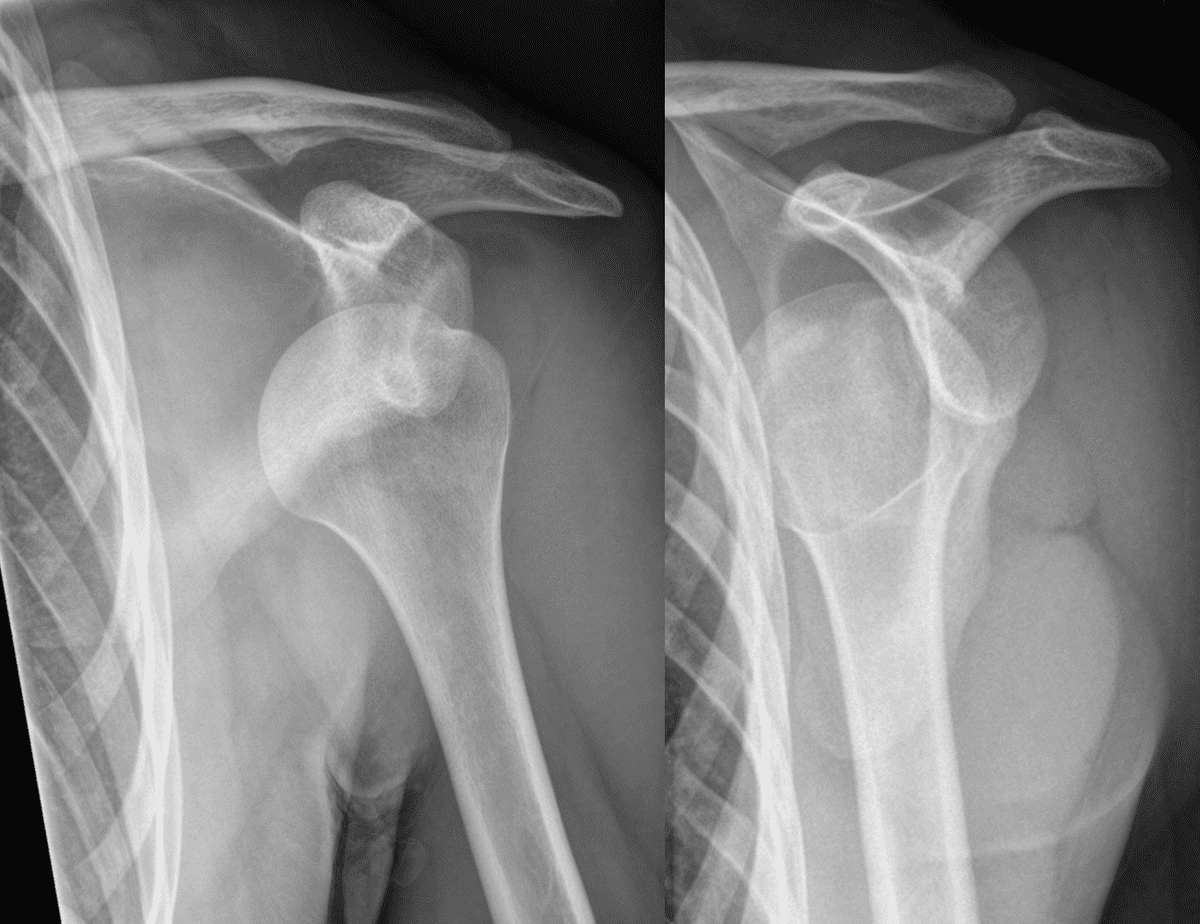

Once the Should Dislocation is back in place, repeat x-rays are performed to ensure it is indeed in the correct position, and to evaluate for other injuries such as fractures. Patients are placed in a sling to rest the shoulder and referred to their orthopedic surgeon for further management.